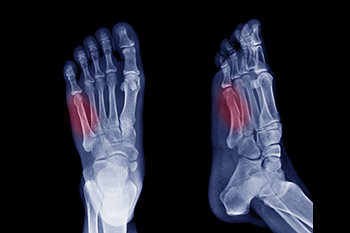

A Jones fracture is a break at the base of the fifth metatarsal bone that connects the foot to the pinky toe. Common symptoms of a Jones fracture are bruising, swelling, and difficulty bearing weight or walking. Jones fractures can result from sudden force on the foot's outer side, often occurring during activities such as sports, dancing, or slips. Traumatic events like inversion sprains during sports or chronic overuse, such as prolonged walking or running on hard surfaces, may contribute to these injuries. Risk factors include participation in high impact activities like basketball or soccer, where sudden movements or pivoting are common. People with high arches may also be more susceptible to this type of fracture. Treatment options include casting and surgical intervention, depending on the severity. If you suspect a Jones fracture or are experiencing foot pain and swelling on the outside of the foot, it is suggested that you make an immediate appointment with a podiatrist for a diagnosis and treatment.

A broken foot is caused by one of the bones in the foot typically breaking when bended, crushed, or stretched beyond its natural capabilities. Usually the location of the fracture indicates how the break occurred, whether it was through an object, fall, or any other type of injury.

Treatment for broken bones varies depending on the cause, severity and location. Some will require the use of splints, casts or crutches while others could even involve surgery to repair the broken bones. Personal care includes the use of ice and keeping the foot stabilized and elevated.